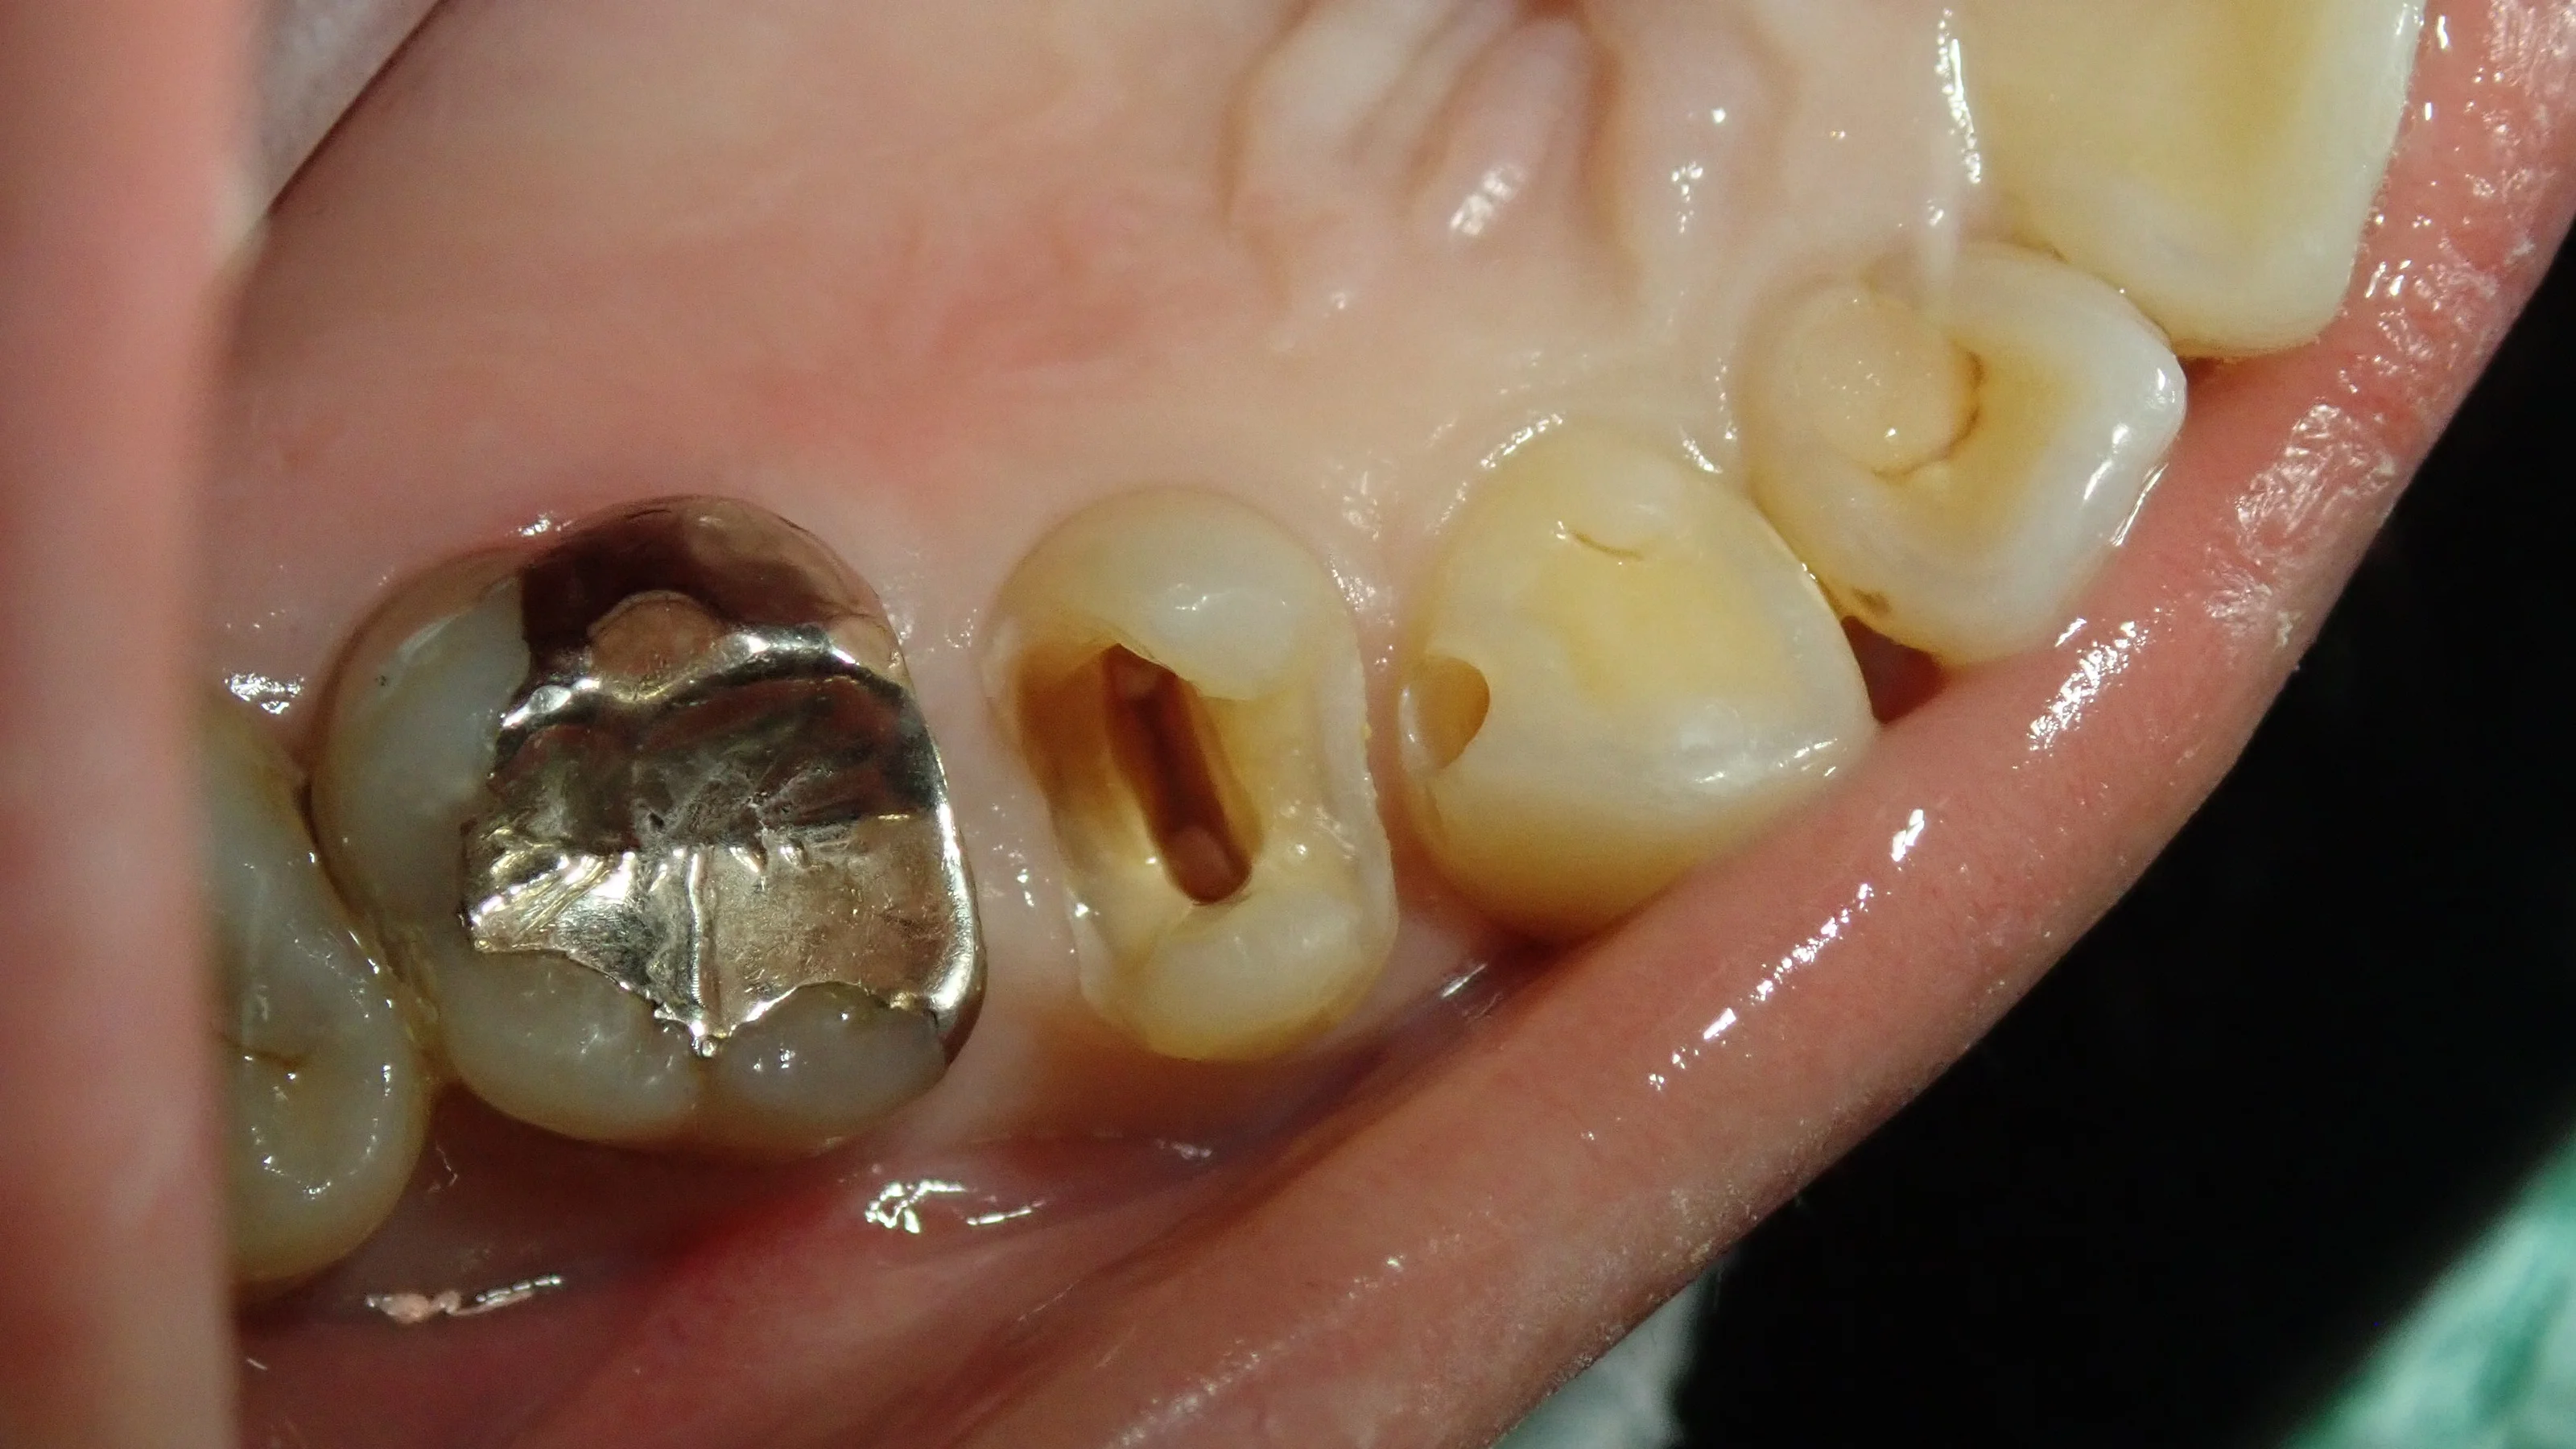

軽く歯を削った状態がこちらです。

じりじりと虫歯が見えてきたのが分かるかと思います。

画面左側の歯は神経の治療後なのですが、レントゲン上では根の先の膿などは確認出来ていませんでした。

ですが、もし虫歯が神経の治療の際に詰められている古い薬にまで到達していた場合は、「まだ膿が溜まっていないだけの状況」と考えられますので、その場合は神経の治療を行う必要があります。